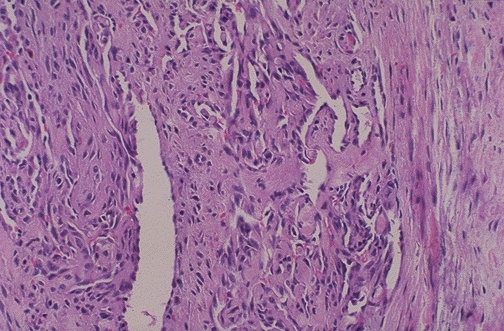

This pelvic vein thrombus demonstrates organization. Note the granulation tissue with capillary proliferation and the attachment of the thrombus to the vessel wall.